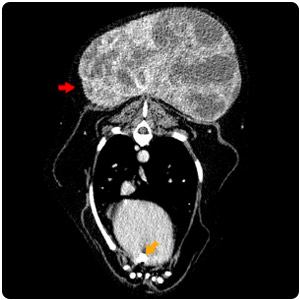

| 右耳腫塊 耳道鼓室泡填塞 |